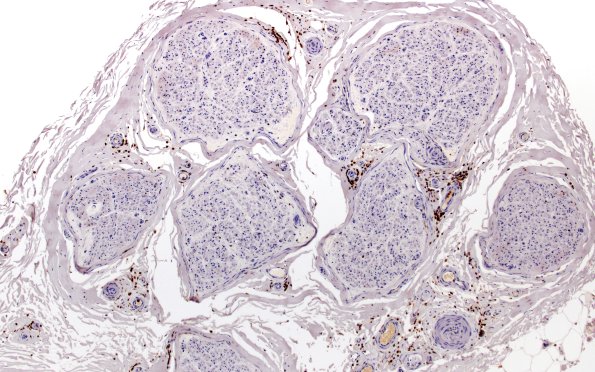

1B1 CIDP (Case 1) CD45 10X

1B1,2 Inflammation is present around epineurial vessels and within the endoneurium. (CD45 IHC)